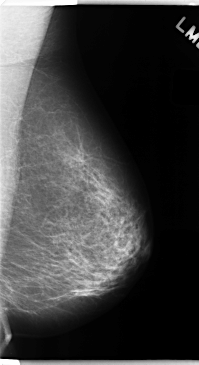

C_0151_1.LEFT_MLO

C_0151_1.LEFT_CC

LEFT_MLO LINES 4736 PIXELS_PER_LINE 2584 BITS_PER_PIXEL 12 RESOLUTION 50 NON_OVERLAY